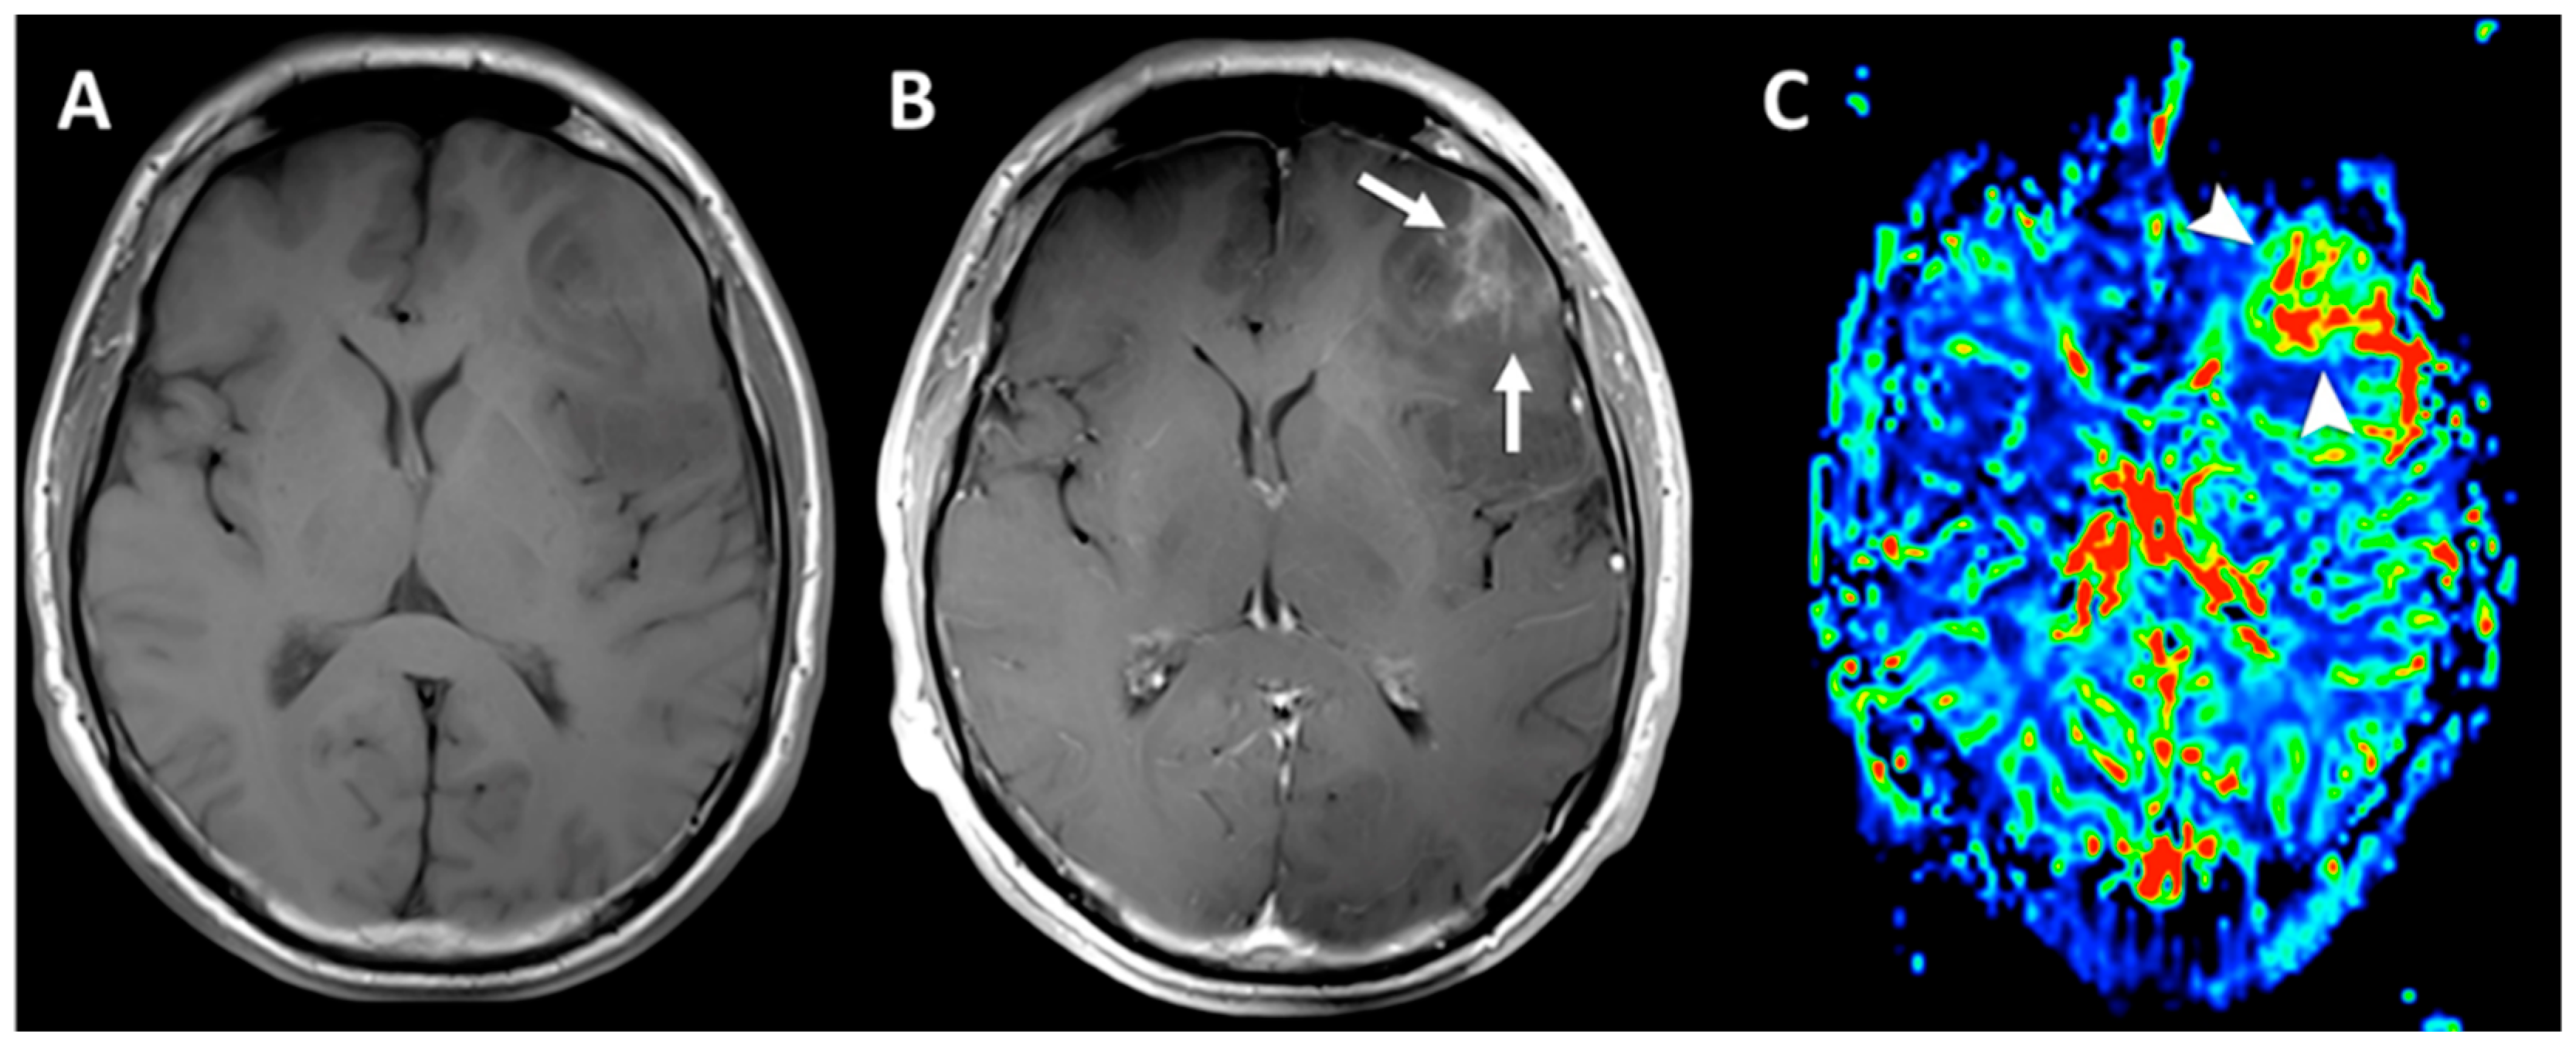

Most T1-based agents currently on the market are classified as extracellular fluid (ECF) agents. This means the agents themselves exert their effects within the ECF, ubiquitous throughout the human body, and do not target a specific organ per se, although the argument can be made that because all of these agents are excreted through renal glomeruli, they preferentially target and accrue in the kidneys [21,22,23]. Regardless, CAs increase T1 relaxation times (R1 = 1/T1) within the extracellular fluid by increasing the relaxivity of water surrounding the gadolinium ion, increasing T1-weighted signal and leading to bright enhancement on imaging. Any pathophysiologic process that causes increased blood flow, fluid extravasation into the interstitial space or breakdown of otherwise impermeable biologic barriers, is prone to abnormal enhancement in response to CA-guided MRI imaging [22,24]. The initial clinical indication for contrast agents was to enhance imaging of the central nervous system [2]. Many tumors, including glioblastoma multiforme, an extremely aggressive form of brain cancer, cause regional breakdowns of the blood–brain barrier; this allows CAs to pass into the brain parenchyma, which otherwise would have been prevented by the impermeable blood–brain barrier (Figure 2). The result is abnormal T1 enhancement on MRI, and increased diagnostic sensitivity [25]. Other clinically relevant examples involving ECF agents include CA-enhanced breast examinations, for the detection of breast cancer, and CA-enhanced prostate examinations, also for the detection of cancer [24].

Figure 2.

Axial T1-weighted (A) post-contrast axial T1-weighed FSE acquisition. (B) A focal region of heterogeneous enhancement (white arrows) indicating disruption of the blood–brain barrier, a finding usually seen in malignant gliomas. Dynamic susceptibility contrast (DSC) perfusion images were also acquired. During the first pass, a Gd-based CA to explore the T2* effects and post-processed rCBV map (C) demonstrates a focal area of markedly increased tumor vascularity (arrowheads) matching the area of enhancement. This area was targeted for stereotactic biopsy, which confirmed the suspicion of an anaplastic glioma. Reproduced with permission from [6].